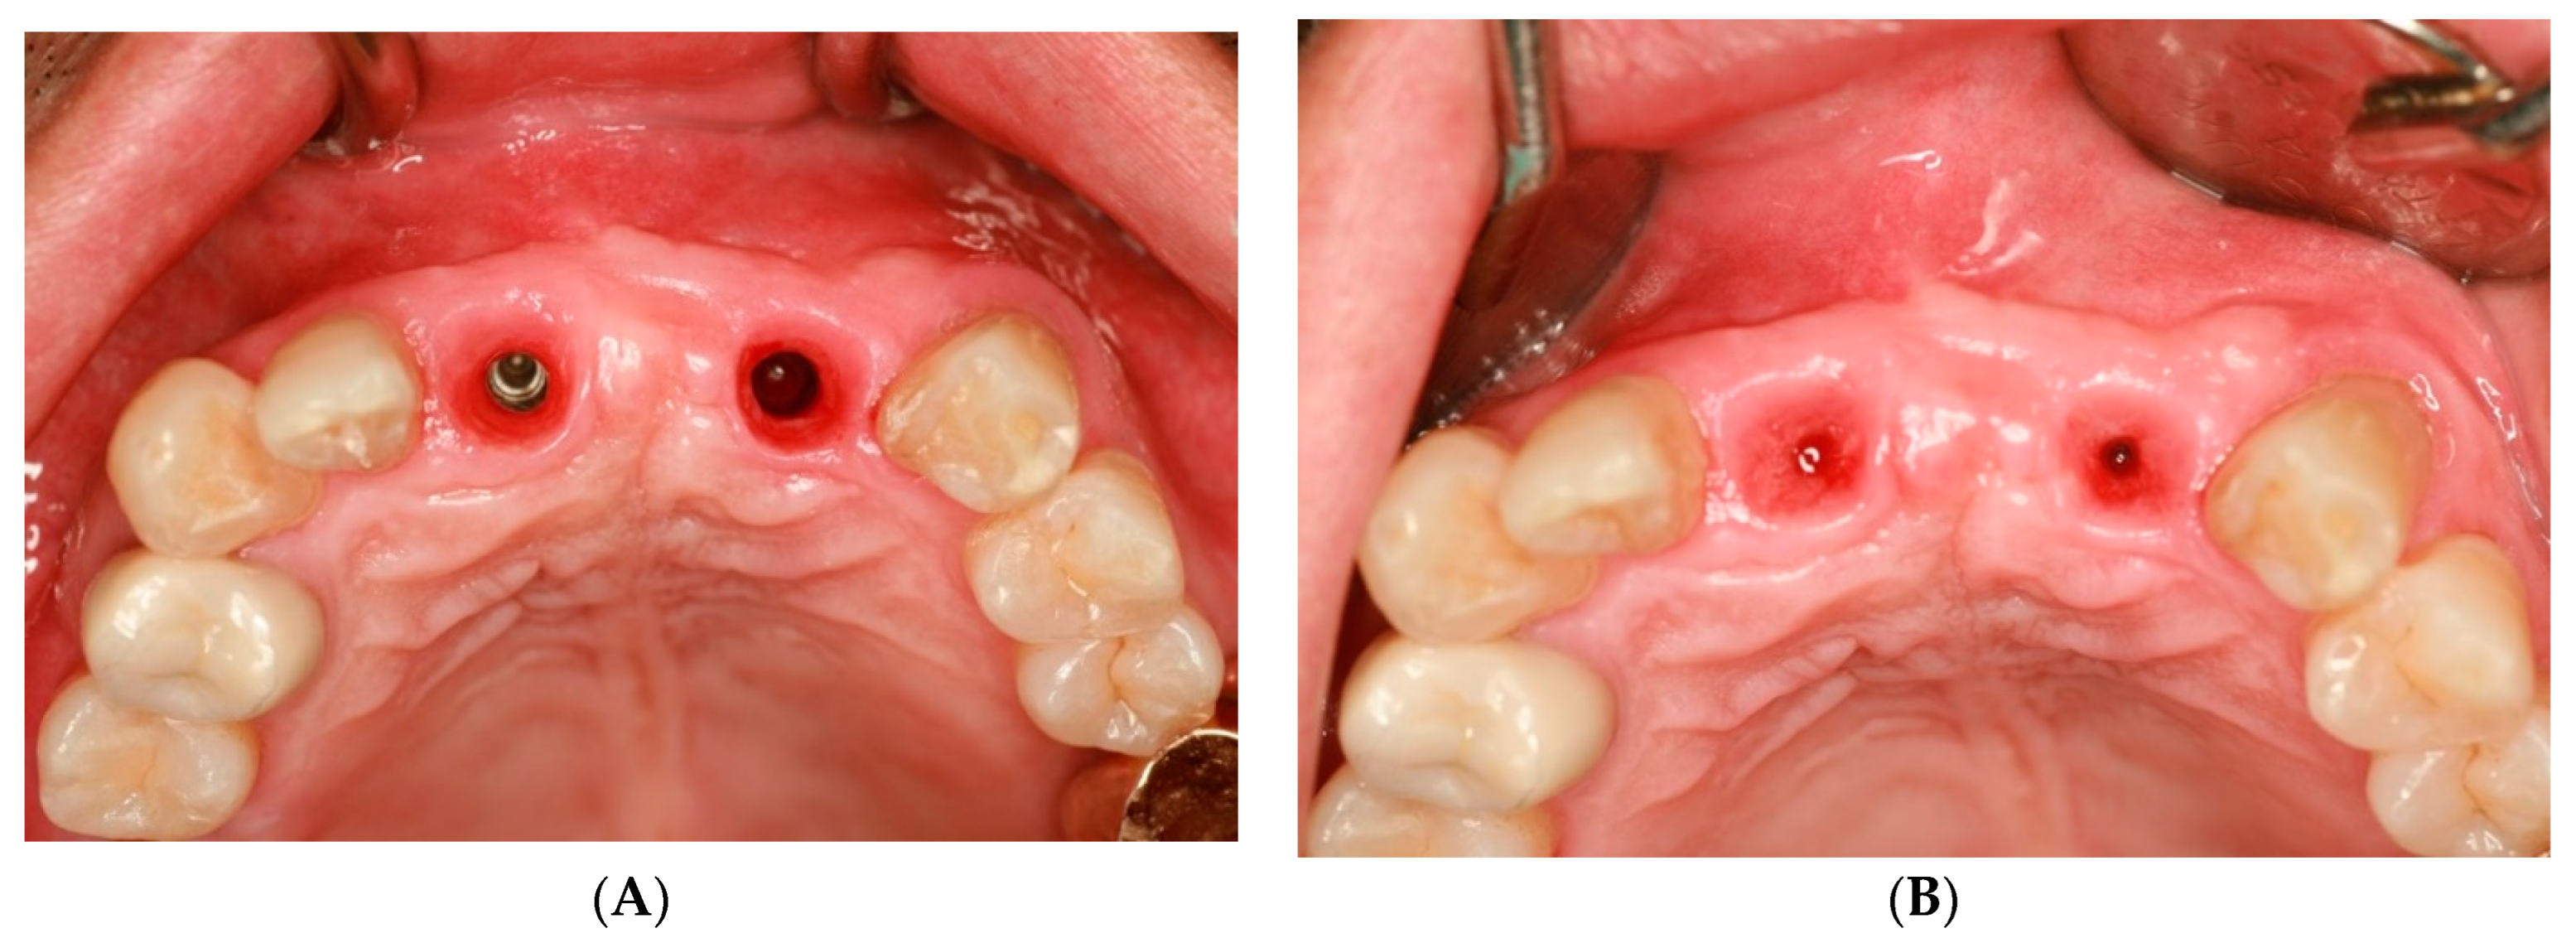

2. Case Presentation

3. Radiographic and Clinical Findings